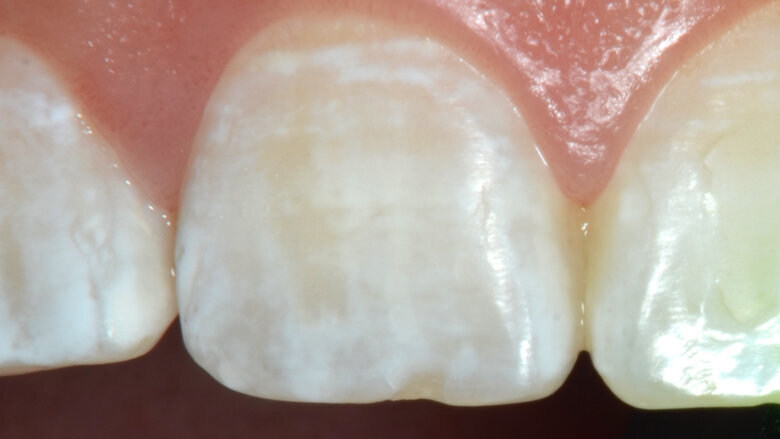

Foto 1. Caso inicial: manchas blancas generalizadas.

Paciente femenino, 20 años, presencia de manchas blancas generalizadas, no presenta sensibilidad, no se ha realizado ningun tipo de aclaramiento dental (Foto 1).